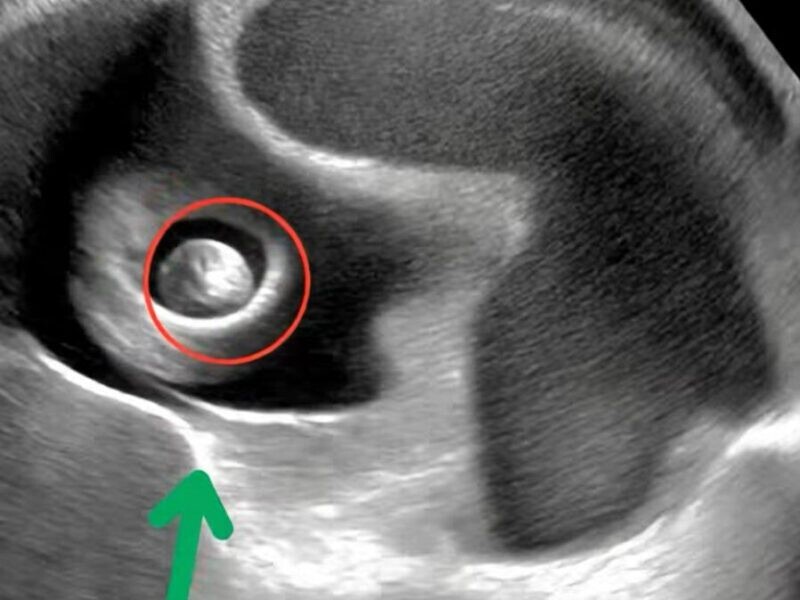

Τι είναι όμως ακριβώς η VITT; Πρόκειται για μια σπάνια, επείγουσα και δυνητικά καταστροφική ανοσολογική θρομβωτική κατάσταση, που συνήθως εμφανίζεται 5 έως 30 ημέρες μετά από εμβολιασμό με εμβόλιο φορέα αδενοϊού. Χαρακτηρίζεται από θρόμβωση σε ασυνήθιστα σημεία, όπως οι φλεβώδεις κόλποι του εγκεφάλου ή οι φλέβες της κοιλιάς, μαζί με χαμηλά αιμοπετάλια και αντισώματα anti-PF4. Συμπτώματα που σηκώνουν κόκκινη σημαία είναι ο πολύ έντονος πονοκέφαλος, οι αλλαγές στην όραση, ο επίμονος πόνος στην κοιλιά ή στην πλάτη, η δύσπνοια, ο πόνος ή το πρήξιμο στο πόδι, αλλά και οι ασυνήθιστοι μώλωπες ή η αιμορραγία. Αυτή η εικόνα χρειάζεται άμεση ιατρική αξιολόγηση και όχι αναμονή.